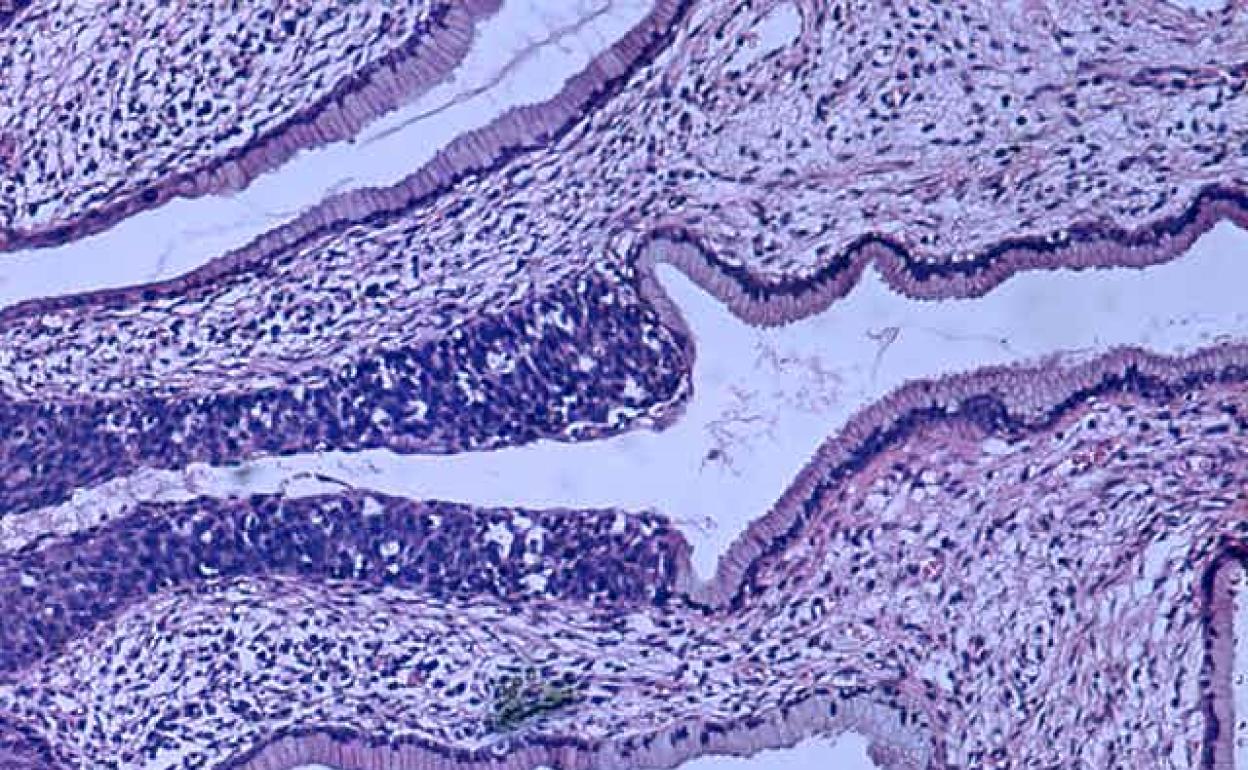

La vacuna contra el VPH ha demostrado ser segura y muy eficaz en la prevención de las infecciones producidas por los diferentes tipos de VPH incluidos en las vacunas. También para las lesiones precancerosas de cuello uterino, vagina, vulva y ano asociadas a dichas infecciones y las verrugas anogenitales.

Aunque hasta ahora la literatura publicada ponía de manifiesto de forma incontestable la eficacia y la efectividad de las vacunas para prevenir las lesiones premalignas secundarias a la infección por el VPH, recientemente se han publicado nuevos datos en relación a la prevención del CCU.